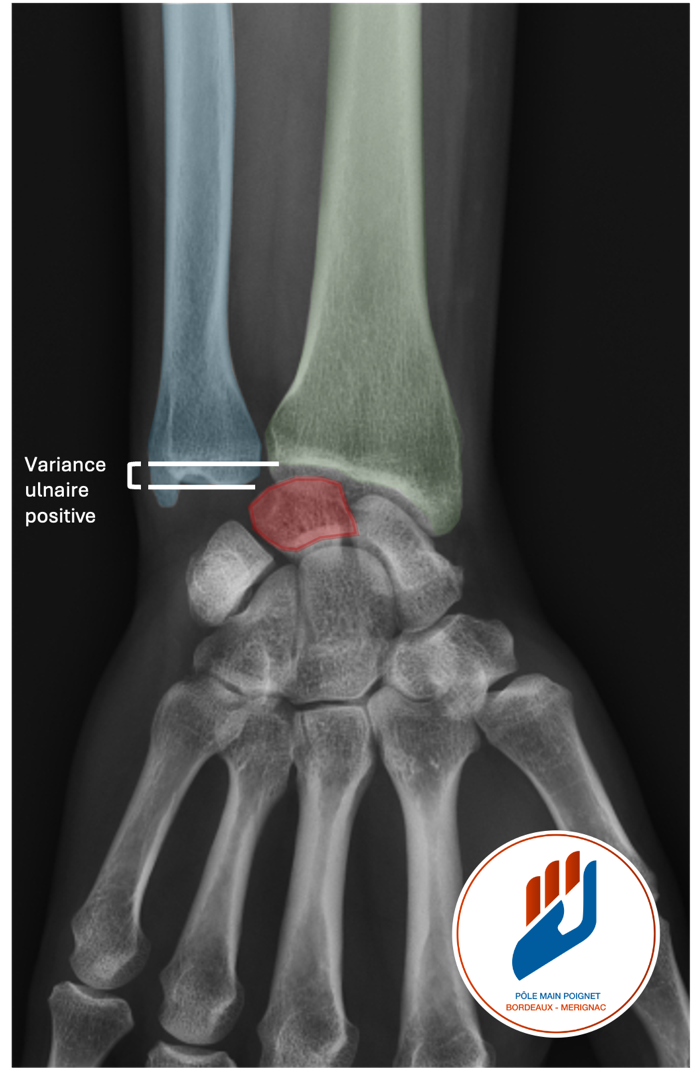

Ce phénomène est particulièrement fréquent lorsque le cubitus (en bleu sur la photo) est plus long que le radius (en vert sur la photo), une configuration anatomique appelée variance ulnaire positive. Cette situation peut être d’origine constitutionnelle, ou apparaître secondairement après une fracture du radius. L’usure mécanique qui en résulte peut engendrer une douleur persistante, surtout lors des mouvements de rotation (comme tourner une clé ou visser un objet), ou à l’appui sur la main.

Des examens d’imagerie sont ensuite prescrits pour confirmer le diagnostic. Les radiographies standards du poignet permettent de mesurer la longueur relative du radius et du cubitus (variance ulnaire). Une IRM ou un arthroscanner permet de visualiser les lésions du fibrocartilage triangulaire et l’état des surfaces articulaires (le cercle rouge sur la photo montre une usure du cartilage sur le pôle proximal du semi-lunaire).